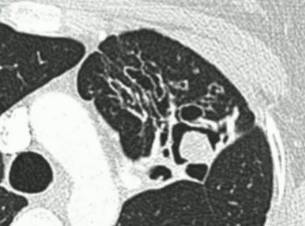

慢性空洞性肺曲霉病(CCPA):最常见,单发或多发的肺空洞(薄壁或厚壁),空洞内可包含一个或多个曲菌球或不规则的腔内物质,具有曲霉菌血清学和微生物学依据,并有明显肺部和全身症状,至少3个多月的视察有放射影像学进展(新发空洞,空洞外周浸润增加及纤维增生增加)。

曲霉结节:不常见,单发或多个结节(<3cm),有或没有空洞,常出现坏死,但不表现为组织侵袭。易与结核、肺癌、肺球孢子菌及其他疾病混淆,只能依靠组织学明确诊断。

亚急性侵袭性肺曲霉病(SAIA):轻度免疫缺陷的侵袭性肺曲霉病患者,发生在1-3个月内,具有可变的影像学特征,包括空洞、结节、有“脓肿形成的进展性实变”。最重要的特征为肺组织发现菌丝,另血液或呼吸液GM试验呈强阳性。